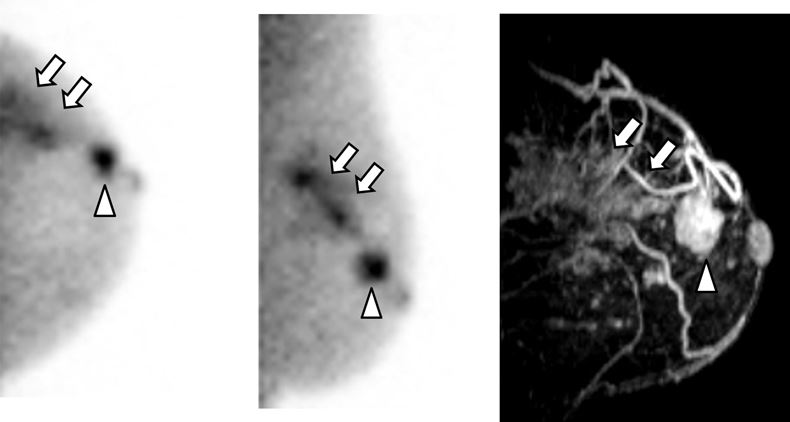

Article: Usefulness of feature analysis of breast-specific gamma imaging for predicting malignancy

Authors: Eun Kyoung Choi, Jooyeon Jamie Im, Chang Suk Park, Yong-An Chung, Kijun Kim, Jin Kyoung Oh